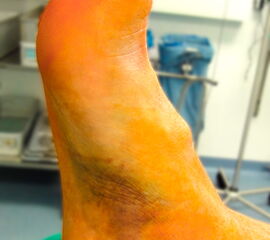

Bei den peripheren Talusfrakturen projizieren sich die Schmerzen meist in den Verlauf der Bandstrukturen 7. Bei polytraumatisierten Patienten ist eine Fremdanamnese und entsprechend gründliche, ggf. wiederholte klinische Untersuchung unerlässlich 13. Zudem sollte vor allem bei Luxationsfrakturen der Ausschluss eines Kompartmentsyndroms bzw. Hautnekrosen erfolgen. Im Zweifel und vor allem bei hochgradig geschlossenem Weichteilschaden sollte die Indikation zur Entlastung mittels Dermatofasziotomie großzügig gestellt werden. Wunden bei offenen Frakturen sollten erst im Operationssaal bzw. im Vorbereitungsraum beurteilt werden, um eine zusätzliche Kontamination mit Krankenhauskeimen zu vermeiden.

Aufgrund des vulnerablen Weichteilmantels im Bereich des Sprunggelenks weisen dislozierte zentrale Talusfrakturen (Korpus, Hals) häufig Störungen der Hauttrophik auf. Dislokationen sind meist augenfällig (Abb. 2) und die dislozierten Fragmente lassen sich perkutan tasten. Zudem ist meist eine abnorme Fußfehlstellung bei Luxationsmechanismen erkennbar. Hier ist insbesondere bei Fragmentdruck auf die periphere Durchblutung zu achten. Eine initiale Dopplersonografie oder die Indikation zur Kompartmentdruckmessung sollte durchgeführt werden.